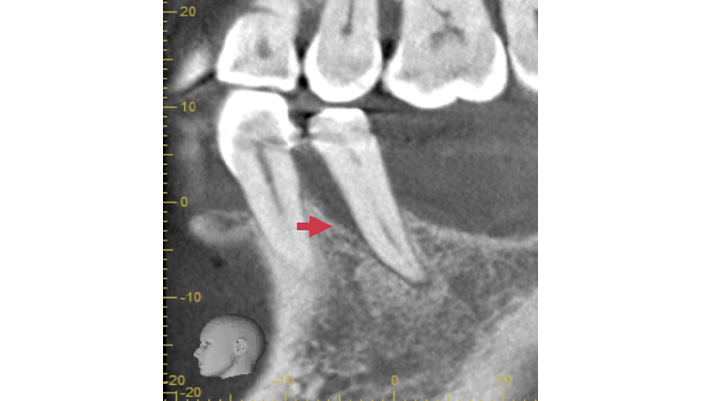

治療中

拡大視野下でむし歯の感染部位を丁寧に除去し、歯髄の状態を確認した結果、神経を残せる可能性があると判断しました。そのため、MTAを用いた歯髄温存療法を選択しました。歯の神経は歯に栄養や水分を供給する重要な役割があり、神経を残すことは歯の寿命を守ることにもつながります。

| 主訴 | 冷たいものがしみる・虫歯を指摘された |

|---|---|

| 治療期間 | 1〜3回 |

| 治療費 | ¥33,000 |

| 治療内容 | 虫歯を除去後、歯髄を保護する薬剤を使用し神経を残す治療を行いました。 |

| 治療のリスク | 術後にしみる症状が出ることがあります。症状が改善しない場合は神経の治療が必要になることがあります。 |